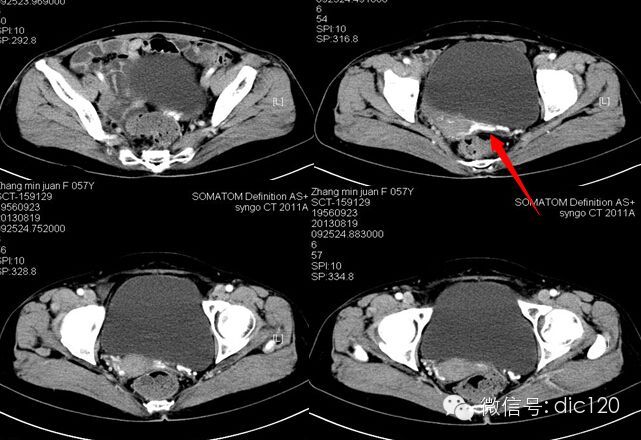

F,56Y,左腰腹部疼痛3天,B超:左肾积水,左输尿管上段扩张。

2013-8-20全麻下行“左肾盂输尿管连接部纤维束带松解 左输尿管纵切横缝术:术中沿腰大肌前方找到输尿管,将输尿管游离至肾盂处,见一纤维束带样组织压迫输尿管,将该组织松解切断,断端结扎,探查见肾盂输尿管连接处输尿管较细,于该处输尿管壁缝两针牵引线,尖刀片纵形切开输尿管壁。

结果:卵巢静脉综合征,患者有外压性输尿管梗阻,卵巢静脉与输尿管交叉处有粘连。